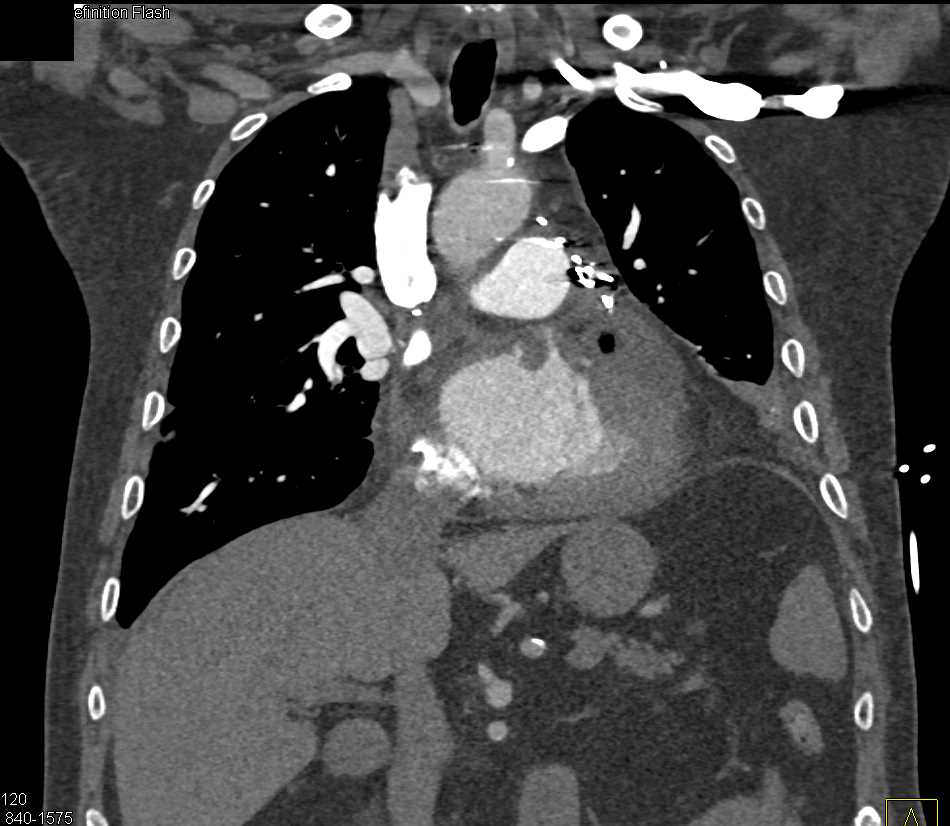

Diagnosis

Post Cardiac Surgery Changes